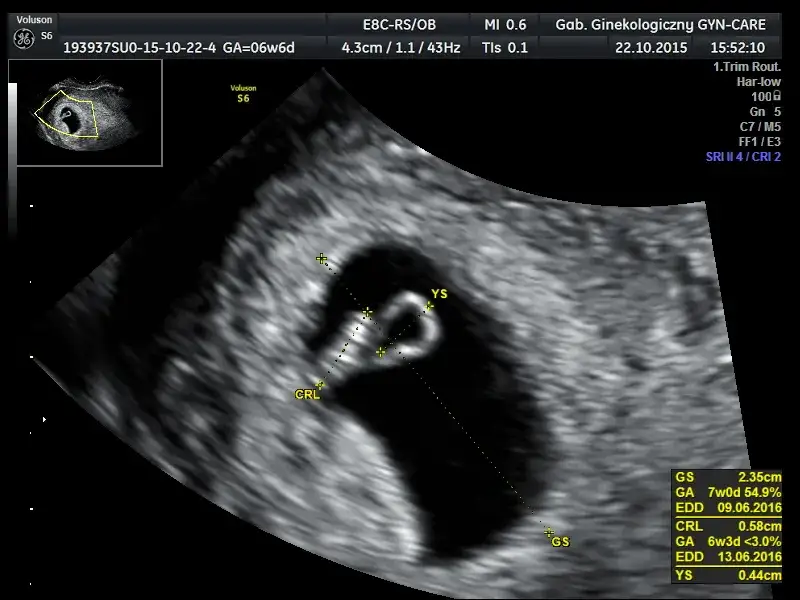

Oto, czego możemy spodziewać się na ekranie ultrasonografu w kolejnych tygodniach ciąży (licząc od pierwszego dnia ostatniej miesiączki):

- Na przełomie 4. i 5. tygodnia ciąży (czyli około 2-3 tygodnie po zapłodnieniu) zazwyczaj widoczny jest w jamie macicy mały, ciemny pęcherzyk ciążowy.

- Około 6. tygodnia ciąży w pęcherzyku ciążowym powinien być już widoczny zarodek oraz, co najważniejsze, jego bijące echo serca. To jest ten moment, kiedy możemy z całą pewnością potwierdzić żywą ciążę.